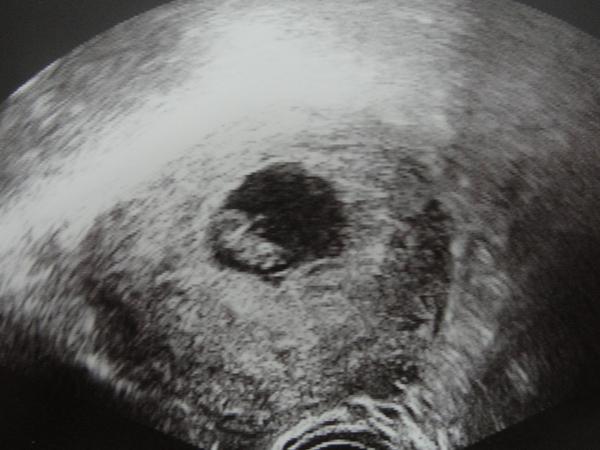

Takže už sme domka a všetko dopadlo na výbornú !!! zodpovedáme 8tt máme 13mm a termín pôrodu 29.7.2013,,, 😵

Pán doktor ked nás zbadal hned povedal,že aký ste veľkí 😵 a srdiečko sme s mm počuli nádherná melódia 😵 😵 😵